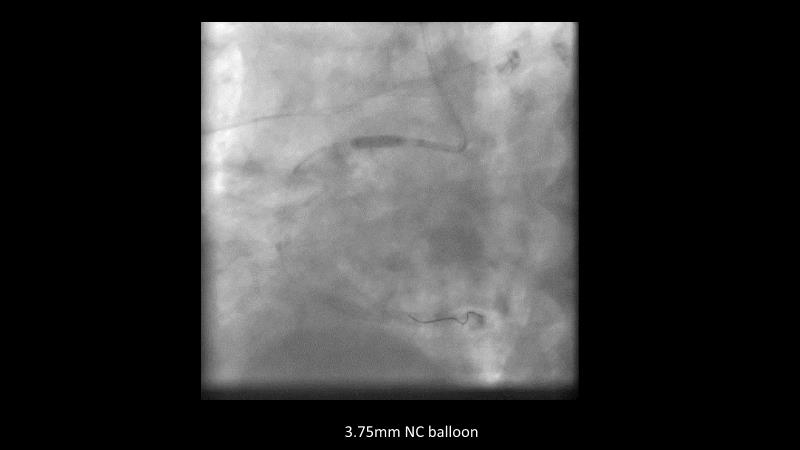

Maximize patient clinical outcomes in complex percutaneous coronary interventions (PCIs) by joining this session. Discover how accurate patient evaluation, advanced imaging/functional modalities, optimized procedures, and the Cre8 EVO device contribute to improved safety and efficacy, and review the challenges associated with DES implantation in complex PCIs.

- To find out how an accurate evaluation of patient profile, imaging/functional modalities, optimised interventional procedure and the proper selection of the device contribute to maximise patient clinical outcomes both in terms of safety and efficacy